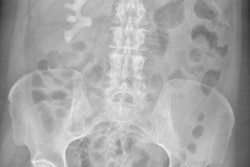

Rayos X digital del abdomen muestra un cálculo renal "cuerno de ciervo," que es la densidad blanca bajo las costillas. Pero, ¿son de gran valor estas investigaciones cuando la TC y el ultrasonido son más sensibles?Con el fin de examinar la eficacia de la radiografía abdominal en la evaluación del dolor abdominal agudo y de proporcionar evidencia para un cambio en la práctica de imaginería, Yamamoto y sus colegas condujeron un análisis retrospectivo de los rayos X abdominales obtenidos en admisiones agudas al departamento de urgencias y de cualquier imagen obtenida posteriormente por TC o ultrasonido. Incluyeron sólo pacientes que se quejaron de dolor abdominal, mayores de 16 anos y remitidos inicialmente para una radiografía abdominal.